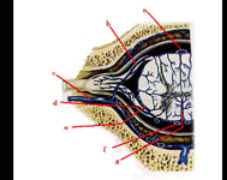

45、填空题

如图为脊髓横断面静脉血供图请标出a___________b___________c____________d______________e____________f______________g_________________。

如图为脊髓横断面示意图请标出a___________b___________c_____________d______________e____________f______________g_________________。